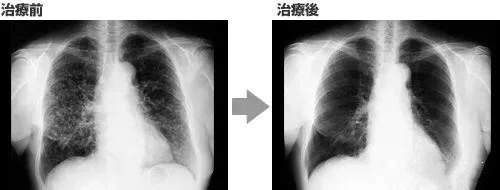

案例 2:国内一名 60 岁的卵巢癌晚期患者,在接受了体外扩增、高度活化的同种异体 NK 细胞的临床治疗后,CA125 水平从 11270 降至 580,所有腹水都消失了。此外,CT 扫描的肿块体积减小,并且没有出现副作用。 案例 3:一名广泛期小细胞肺癌患者,在进行 4 个疗程化疗和 4 次高度活化 NK 细胞临床干预后,患者第一次进行治疗后的 CT 复查结果显示,肿瘤缩小到了原来的 1/8。而且在距发病第六年的 CT 复查中,仍旧没有发现任何异常及复发的迹象。